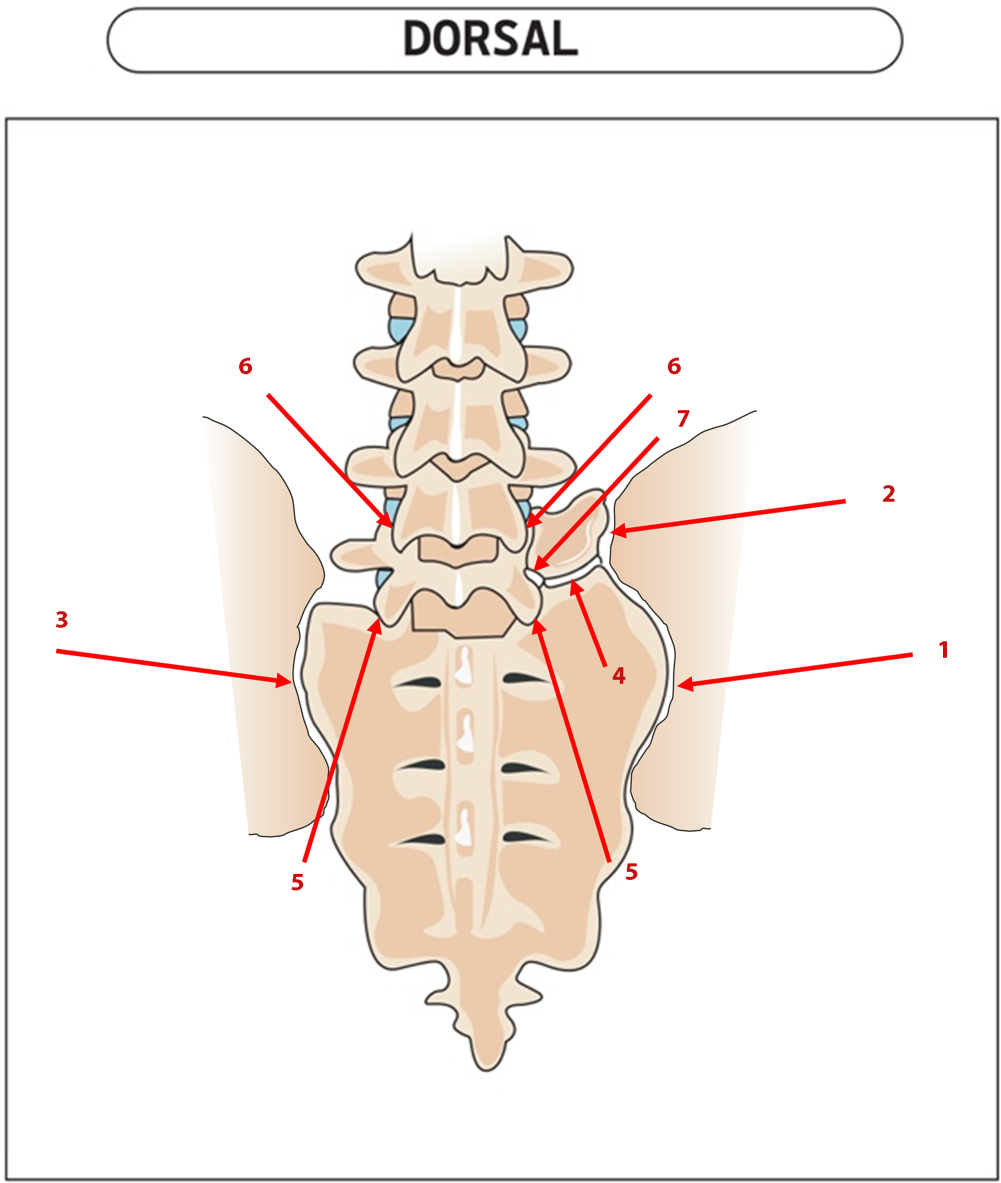

Bei radiologischem LSTV-Nachweis mit passender Klinik sind diagnostische Infiltrationen der potenziellen Schmerzgeneratoren hilfreich, wenngleich es keine publizierte Evidenz zu ihrer Wertigkeit gibt (Abb. 3). Die Besserungsrate jeder einzelnen Infiltration ist sicherlich nicht absolutistisch als klarer Beweis für oder gegen eine Struktur als Schmerzursache zu werten, das Konzept der Infiltrationsabklärung kann aber dennoch wertvolle Hinweise liefern, um das weitere Vorgehen beim individuellen Patienten zu planen.

Abb. 3

Infiltrationsmöglichkeiten. 1 Iliosakralgelenk (ISG) kaudal des Neoarthros, 2 ISG kranial des Neoarthros, 3 ISG der Gegenseite, 4 horizontaler Neoarthros, 5 Facettengelenk L5/S1 ipsi- und kontralateral, 6 Facettengelenke L4/5 und 7 Nervenwurzel L5 intraforaminal L5/S1

Bild vergrößern